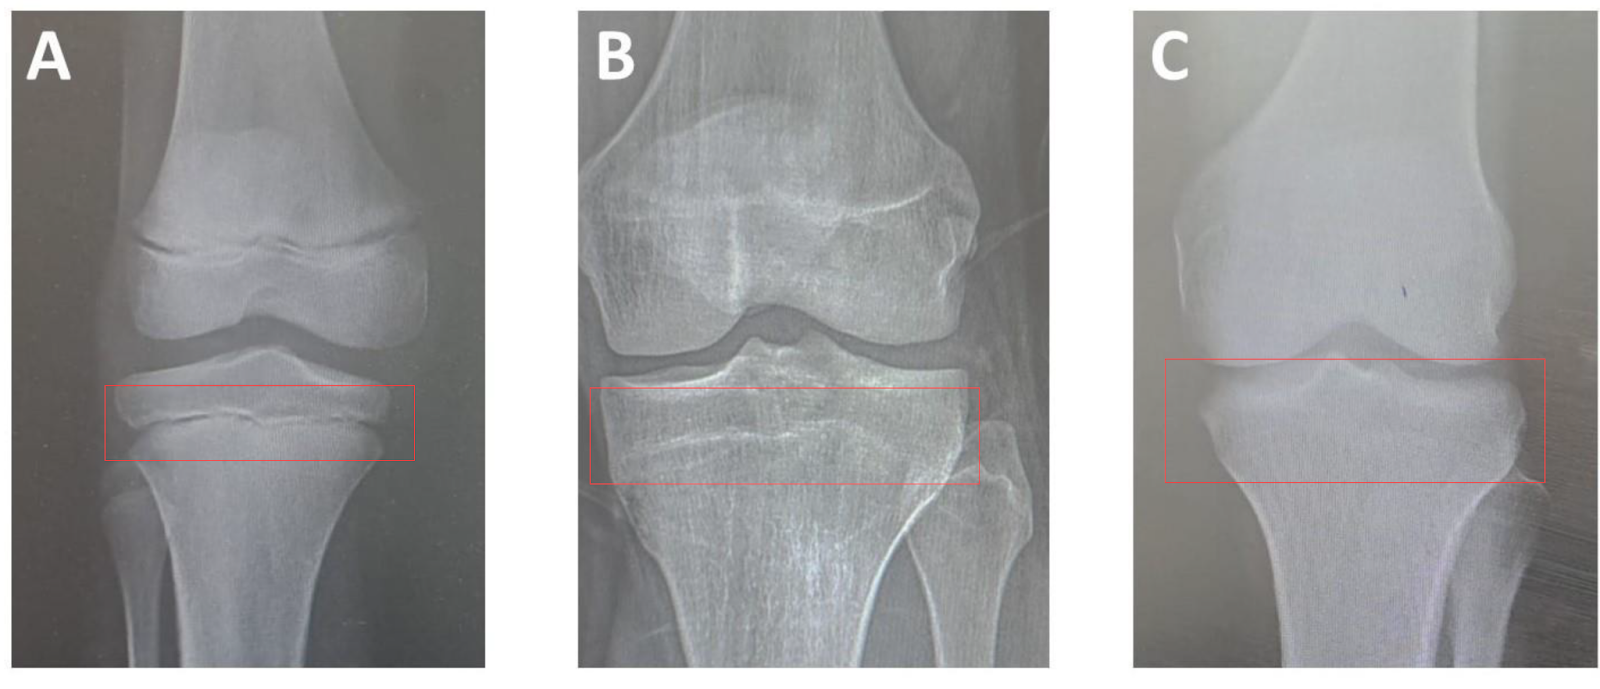

Now, to find out if your growth plates are fused or not, we’re going to look at your wrist & knees for your height, and at your clavicles for your frame.

Above I've added 3 figures, from open ( A ) to fully fused ( C ), those are your growth plates, if theres a visible line like in B, they’re still open, but closer to fusion. ( You will typically see this in X-rays of teenagers). Whereas if you don’t see any lines at all, it means the cartilage has hardened into solid bone, ending any growth potential.

Once again, refer to the graphic above.

If there’s a visible gap or a full line, your growth plates are open, if there’s no visible line, they’re closed.